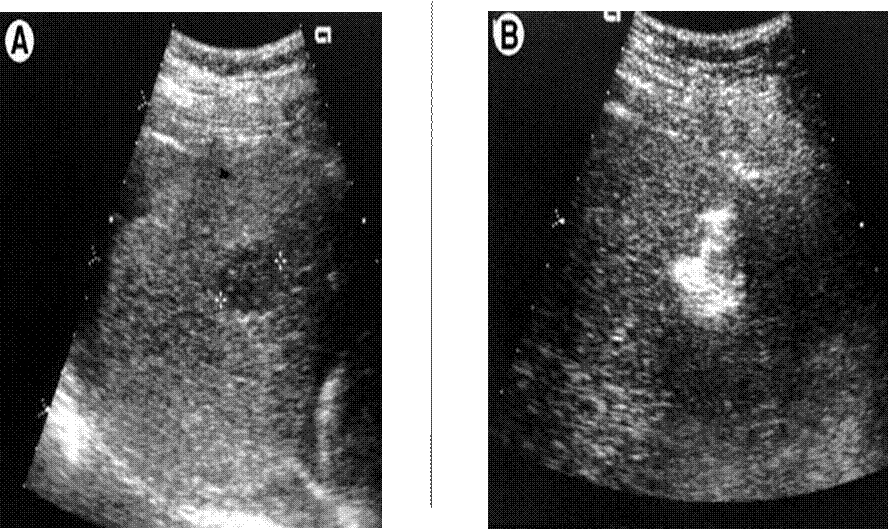

• USS: echogenic spot, well demarcated.

Ultrasound Image of Hemangioma

Ethanol Injection USS